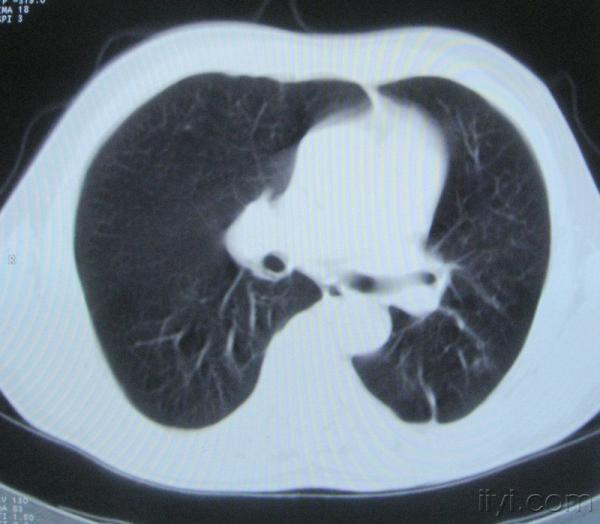

男。60岁,胸片示支气管炎治疗后复查CT。

你指那个肯定是淋巴结,中央系坏死,这很常见,特别在双侧腹股沟会经常看到。这个双侧腋窝及纵隔见多发小淋巴结征。

根据位置考虑应该是淋巴结,密度不均,是因为肿大的淋巴结中心液化坏死